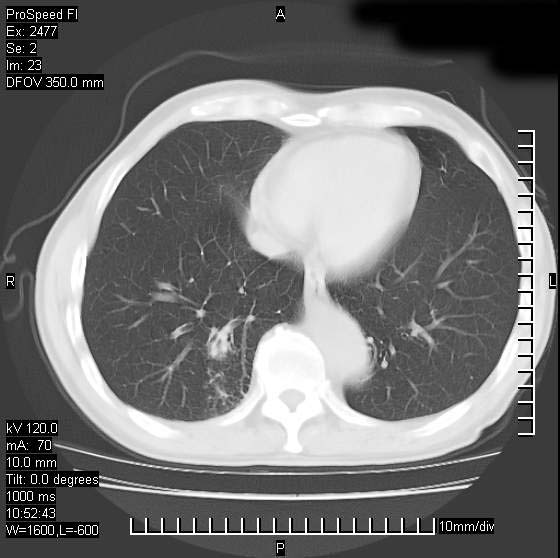

以下是引用天南地北在2007-10-9 14:29:00的发言:[br]1:右上肺结核[br]2:右肺下叶肿块:不支持肺癌,首先考虑炎性病变-肺脓疡可能性大[br]理由:1:临床病史支持,肺脓肿症状不明显应该是不规则服药造成。[br] 2:肿块边缘模糊,周围可见炎性渗出,长毛刺,内见支气管征,不过有点不规则。[br] 我感觉下肺癌这个诊断有点偏左,建议积极抗炎治疗后复查

以下是引用卜一在2007-10-9 15:55:00的发言:[br][br] [br] 1:右上肺结核[br]2:右肺下叶肿块:不支持肺癌,首先考虑炎性病变-肺脓疡可能性大[br]理由:1:临床病史支持,肺脓肿症状不明显应该是不规则服药造成。[br] 2:肿块边缘模糊,周围可见炎性渗出,长毛刺,内见空气支气管征,不过有点不规则。[br] 我感觉下肺癌这个诊断有点偏左,建议积极抗炎治疗后复查![br]支持! [br] [br] [br]

以下是引用wxy7406在2007-10-9 21:02:00的发言:[br]结合临床病史首先考虑感染性病变,但周围型肺癌不能除外,1.患者年龄偏大2.临床有咯血3.(也觉得是最重要的一点)病灶内有偏心性空洞。

以下是引用王仕学在2007-10-9 13:48:00的发言:[br]右下肺周围性肺癌可能性大,最好活检吧

以下是引用hhcckk在2007-10-9 15:18:00的发言:[br]右上肺病灶考虑结核,病灶多种形态并存(纤维化、增殖性病灶并存)[br]右下肺病灶比较难说,个人意见更趋向于“天南地北”的诊断----肺脓肿[br]1、病人有明显的寒战,高热,肿瘤病人很少出现[br]2、病灶周围的肺纹理走向柔和,没有肿瘤病灶常见的集束征[br]3、病灶边缘的毛刺较长,恶性肿瘤多为短毛刺[br]痰中血丝和病人的年龄是两个不利于良性肿块的因素,建议早点活检

以下是引用ydx_74在2007-10-9 15:53:00的发言:[br]右上肺结核,右下中心性肺癌可能大,肺门淋巴结肿大。